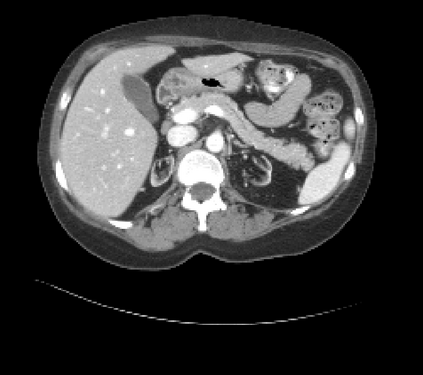

It is imperative to ensure the robustness of deep learning models in critical applications such as, healthcare. While recent advances in deep learning have improved the performance of volumetric medical image segmentation models, these models cannot be deployed for real-world applications immediately due to their vulnerability to adversarial attacks. We present a 3D frequency domain adversarial attack for volumetric medical image segmentation models and demonstrate its advantages over conventional input or voxel domain attacks. Using our proposed attack, we introduce a novel frequency domain adversarial training approach for optimizing a robust model against voxel and frequency domain attacks. Moreover, we propose frequency consistency loss to regulate our frequency domain adversarial training that achieves a better tradeoff between model's performance on clean and adversarial samples. Code is publicly available at https://github.com/asif-hanif/vafa.